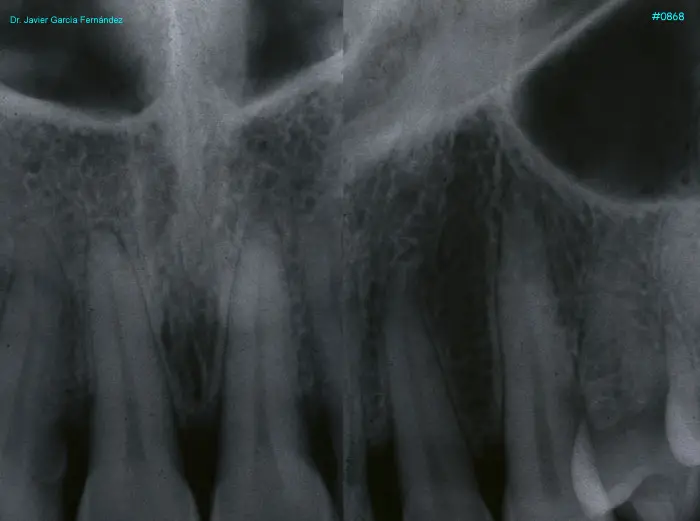

Atlas of Surgical Techniques in Periodontics. Chapter III. Atlas de Técnicas Quirúrgicas en Periodoncia